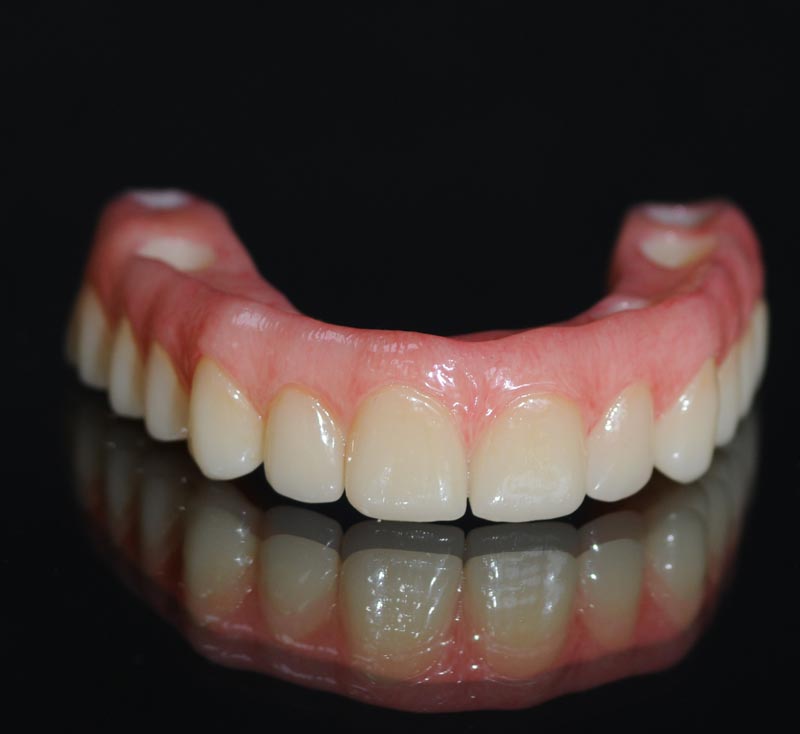

protesi

Provvisorio, che è rapportato alla guida chirurgica per un correto riporto dal progetto al cavo orale